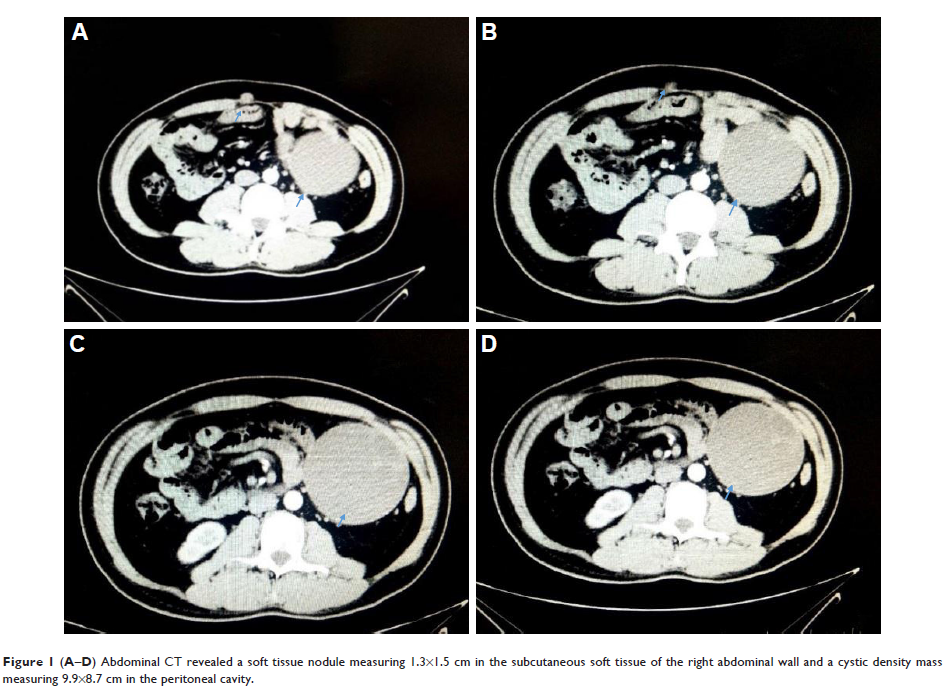

Case Report

- 作者:Hui-Min Chen, Ge Feng

- 期刊:OncoTargets and Therapy